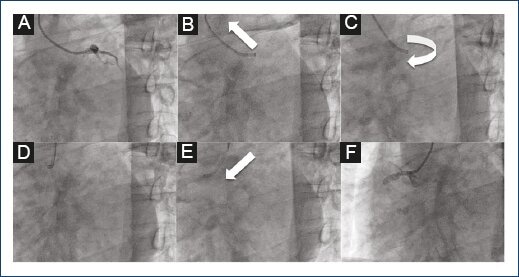

Right artery cannulation was performed by pushing the J-guidewire down toward the aortic valves. The catheter was then pushed down and turned clockwise toward the right coronary cusp. Then, the Guidewire was retracted while pushing the catheter at the same time to cannulate the right coronary artery (RCA) (Fig. 2).

Figure 2 Image which shows the left and right coronary artery cannulation technique. (A-F). Cannulation of the left coronary artery (LCA) which shows contrast injection into the LCA system (A), retraction of the catheter to the ascending aorta to disengage the LCA (B), clockwise 90' rotation of the catheter to change the tip of the catheter to the contralateral sinus (C), stabilization of the catheter on the aorta will allow continuing with changing of the sinus (D), advancement and simultaneous 90' rotation of the catheter down to the aortic root and the right coronary ostium will place the catheter correctly (E), cannulation and contrast injection into the right coronary artery (F).